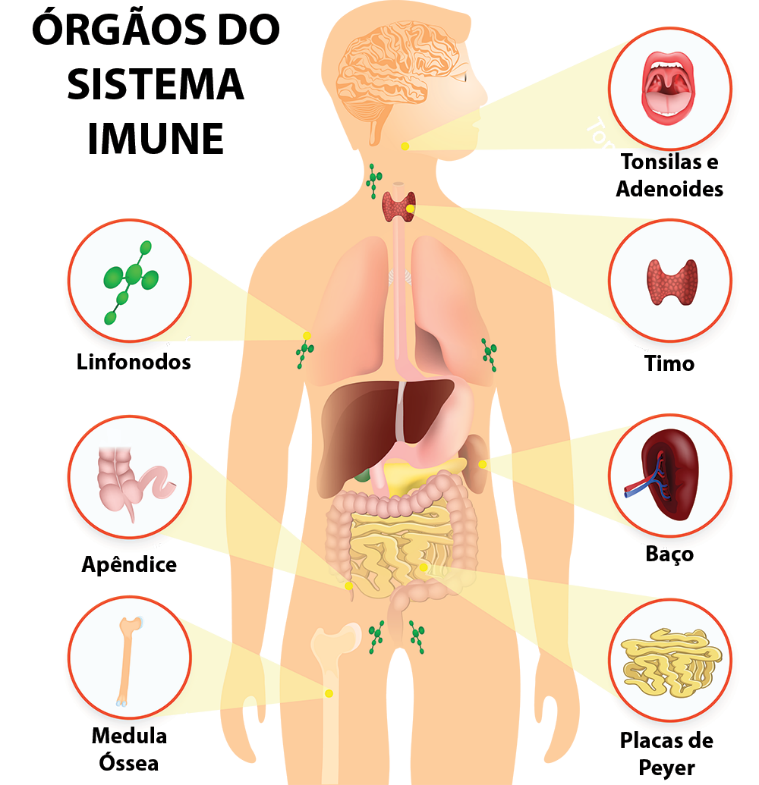

No último post nós abordamos um pouco sobre Sistema Imunológico e as Células que o compõe. Hoje falaremos sobre a Anatomia desse Sistema e as funções dos tecidos e órgãos que o forma.

Pois bem, os órgãos que vão compor os tecidos linfoides são geradores, que podem ser definidos como órgãos linfoides primários ou centrais.

São neles que primeiro os linfócitos vão expressar os receptores de antígenos e vão atingir o que chamamos de maturidade fenotípica e também funcional, além iniciar e desenvolver as respostas dos linfócitos aos antígenos estranhos, a partir de órgãos periféricos, que são normalmente secundários aos anteriores.

Em resumo, anatomicamente, o sistema linfático é uma rede de órgãos linfoides, linfonodos, ductos linfáticos, tecidos linfáticos, capilares linfáticos e vasos linfáticos.

No texto de hoje aprendemos um pouco mais sobre o sistema imune, demos um enfoque aos órgãos que estão associados a esse sistema. E é incrível perceber a distribuição desses órgãos, tecidos e células de forma a nos proteger como um todo, garantindo nosso bem estar, né?